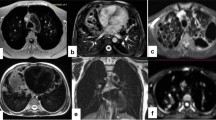

Interlobular septal thickening on ground-glass opacity. 56-year-old male. a End-inspiratory axial CT after 1 month from discharge, b Free-breathing PD-weighted axial image after one month from discharge, c Apparent Diffusion Coefficient Map, and d diffusion-weighted imaging (DWI) free breathing (b = 1000 s/mm2). Note areas of interlobular septal thickening superimposed to a GGO, on both the right and the left lower lobes that do not show restricted diffusion on DWI nor hyperintensity on ADC map

The sensitivity, specificity, accuracy, and positive and negative predictive values of MRI, when considering CT as the standard of reference, in the detection of different parenchymal patterns are detailed in Table 3. The sensitivity was highest for interlobular septal thickening (1.00, 95% confidence interval (CI): 0.91–1.00), consolidation (1.00, 95% CI: 0.63–1.00), and GGOs (1.00, 95% CI: 0.91–1.00) (Fig. 2). Conversely, MRI showed poor sensitivity in the detection of fibrosis (0.18, 95% CI: 0.04–0.43), pleural indentation (0.23, 95% CI: 0.09–0.44), vessel enlargement (0.50, 95% CI: 0.07–0.93), and bronchiolar ectasia (0.00, 95% CI: 0.00–0.18). Specificity was overall very high, except for GGOs (0.25, 95% CI: 0.05–0.57) and interlobular septal thickening (0.64, 95% CI: 0.31–0.89). MRI was not able to detect bronchiolar ectasia in any of the cases.

The main disease pattern, among GGOs, consolidation, interlobular septal thickening, and fibrosis, was detected by both MRI and CT with substantial agreement (k = 0.764). Also, MRI proved to be very reliable in assessing the resolution or progression of radiological signs relative to the previous CT scan, showing almost perfect agreement (k = 0.857) with CT. Of note, very good agreement was confirmed for consolidation and interlobular septal thickening (k = 1.00 and k = 0.734, respectively). However, poor agreement was noted concerning the detection of GGOs (k = 0.339), which pathologically corresponds to partial filling of the alveolar lumen with fluid, macrophages, neutrophils, or amorphous material and which correlates with disease activity [23]. The poor agreement between MRI and CT in the detection of GGOs could be explained by MRI’s greater ability to discriminate the alveolar content by quantifying its PD, showing a relatively much higher signal in lung parenchyma affected by endo-alveolar effusion when compared with normally aerated lungs (Fig. 3). Accordingly, the sensitivity for MRI in detecting GGOs was perfect (1.00, 95% CI: 0.91–1.00) as compared with the very low specificity (0.25, 95% CI: 0.05–0.57). Separately, it is noteworthy that very poor agreement was recorded for the detection of bronchiolar ectasia (k = 0.000). These data confirm previous findings by Ciet et al. [24], who reported the superior sensitivity of CT when evaluating changes in the peripheral areas of the lung, such as bronchiolar ectasia. A possible explanation for this could be the lower spatial resolution of MRI as compared with CT, especially when focusing on more distal areas of the lung [25]. To overcome the issue, three-dimensional T1-weighted, gradient-echo sequences might be added to the protocol. However, further studies are necessary to confirm these radiologic and pathologic correlations.

Ground-glass opacity with negative CT. 46-year-old male. a End-inspiratory axial CT after 1 month from discharge, b Free-breathing PD-weighted axial image, c Apparent Diffusion Coefficient Map, and d diffusion-weighted imaging (DWI) free breathing (b = 1000 s/mm2). Note areas of GGO on both the right and the left lower lobes visible on the PD-weighted image not corresponding to any alteration on the CT scan. No restricted diffusion on DWI nor hyperintensity on ADC map depicted